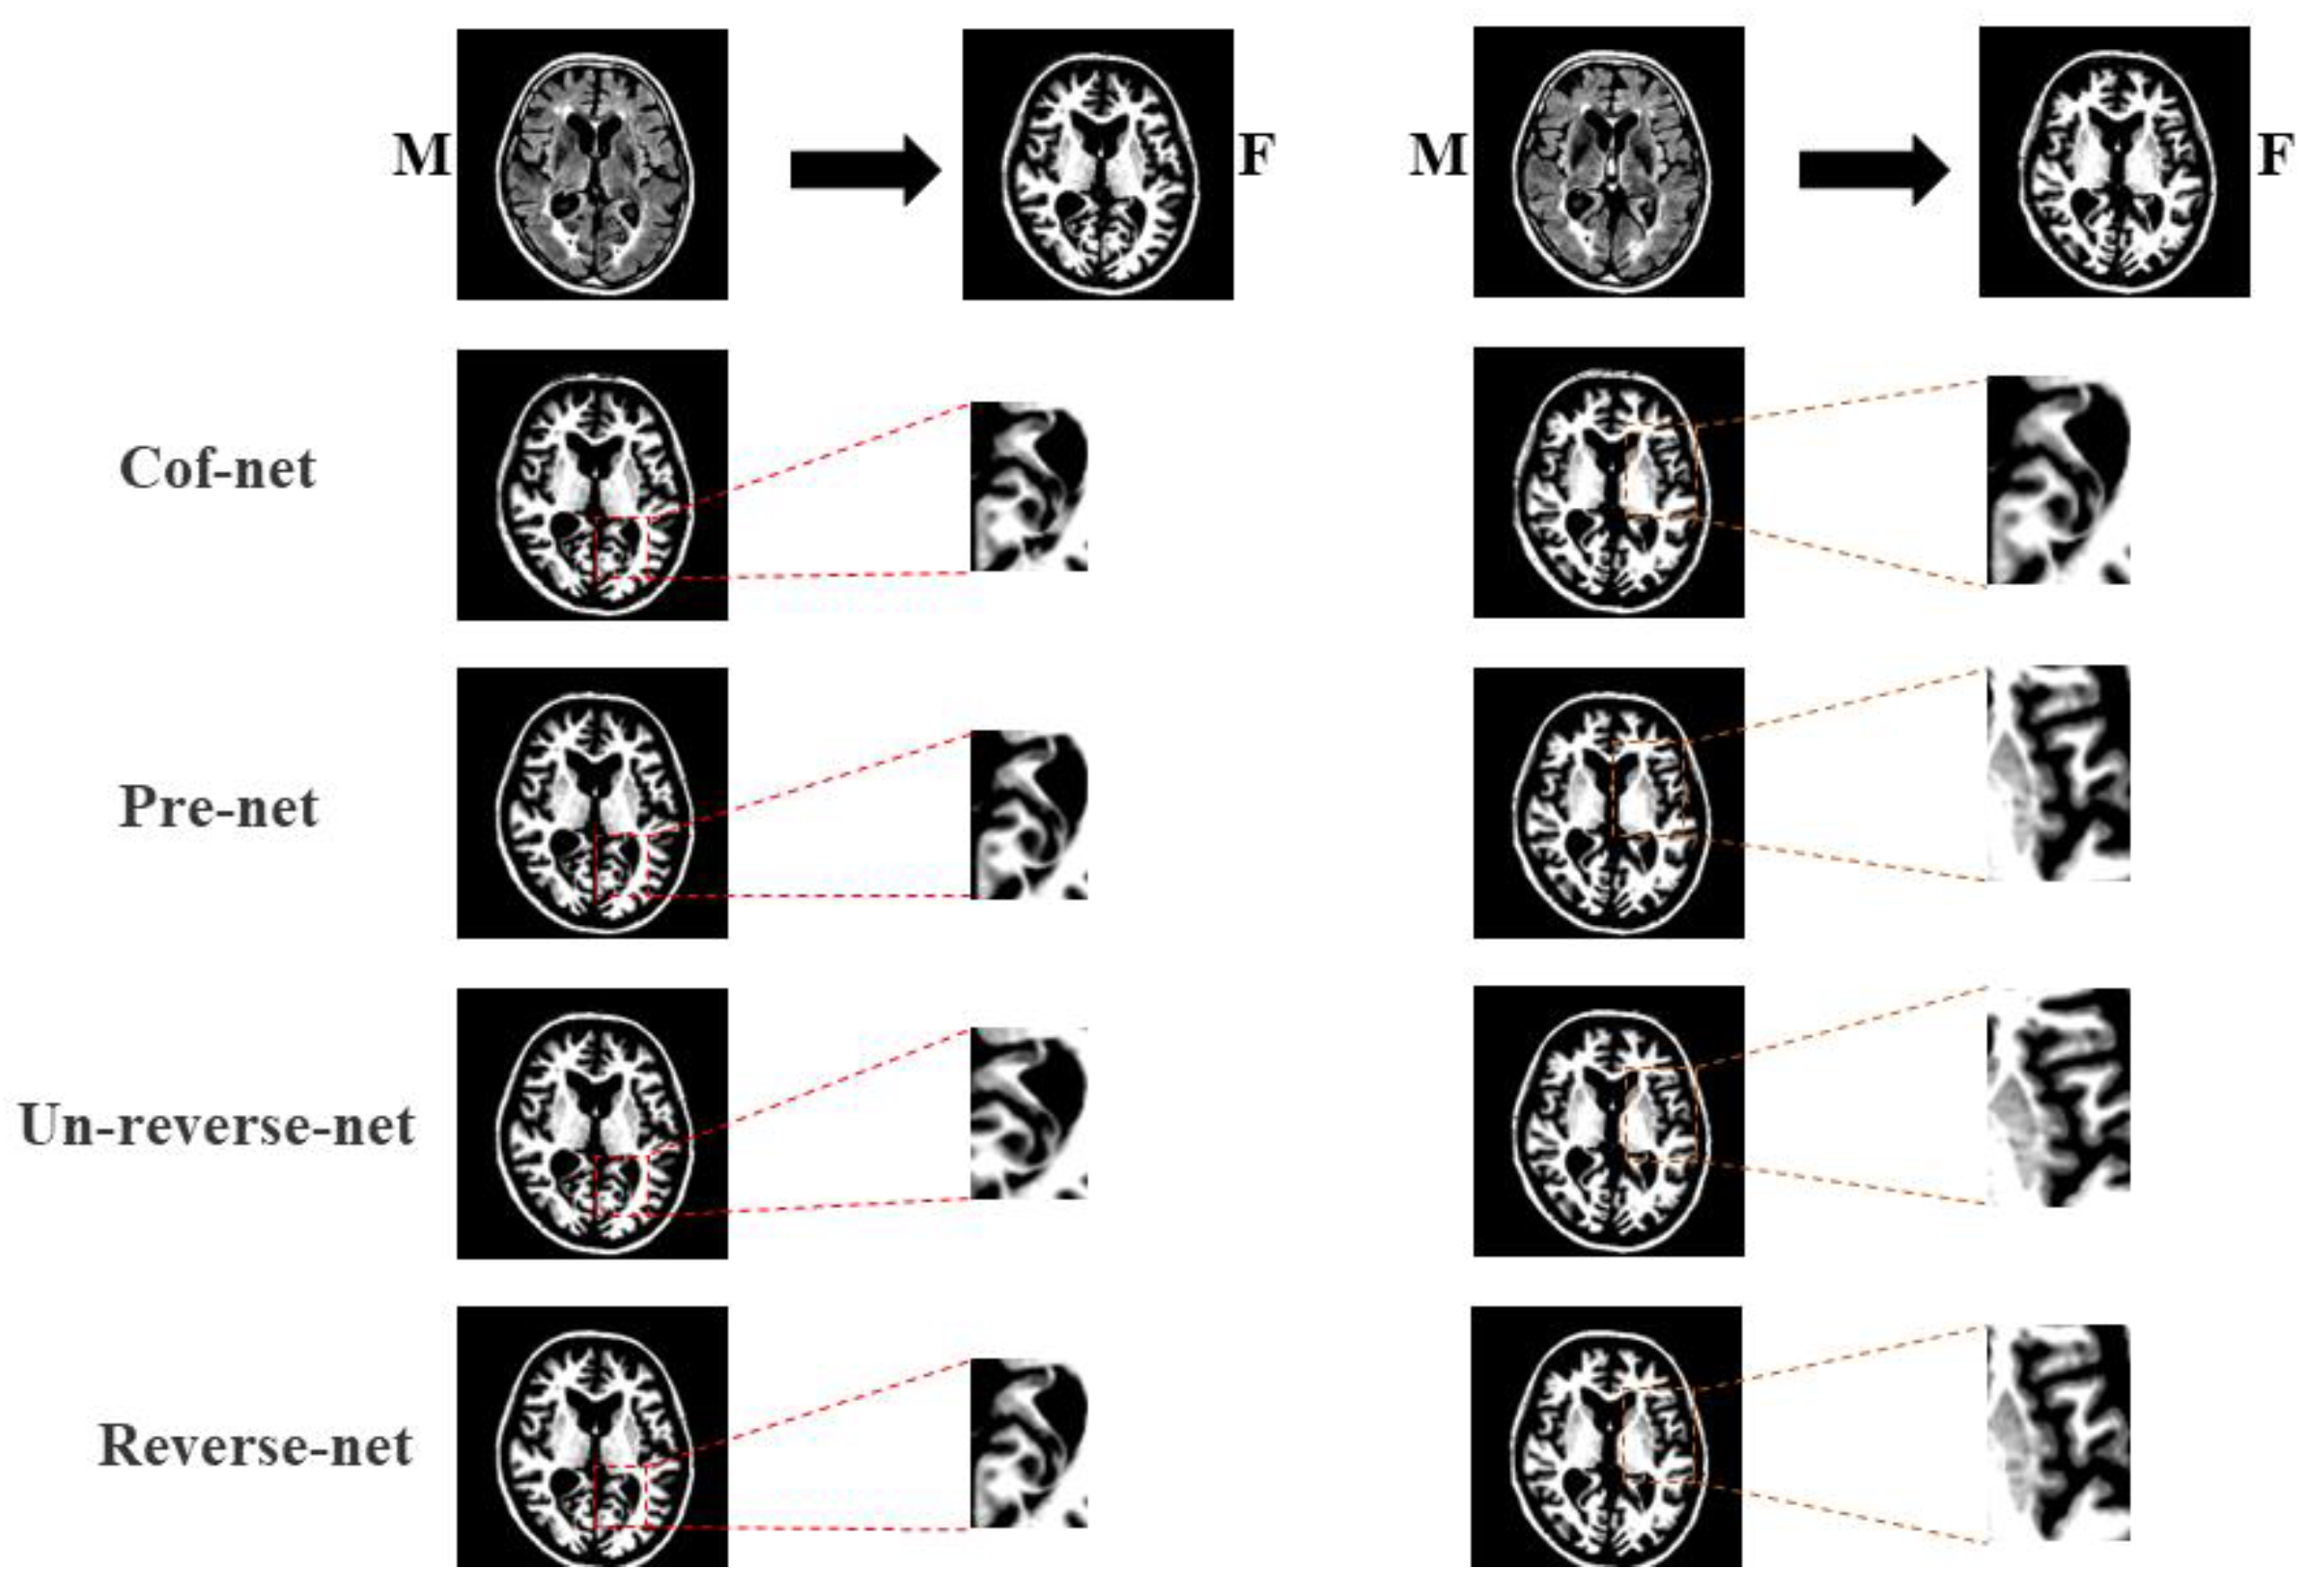

5.2. Ablation Experiment

| Method | DSC (%) | Precision (%) | Det.Jac (%) |

|---|---|---|---|

| Cof-net [46] | 81.70 ± 3.71 | 90.59 ± 3.05 | 0.006 ± 0.002 |

| Pre-net | 84.44 ± 0.67 | 89.94 ± 4.27 | 0.002 ± 0.001 |

| Un-reverse-net | 83.29 ± 0.15 | 89.45 ± 1.23 | 0.004 ± 0.012 |

| Reverse-net | 85.20 ± 1.18 | 94.41 ± 0.89 | 0.004 ± 0.001 |